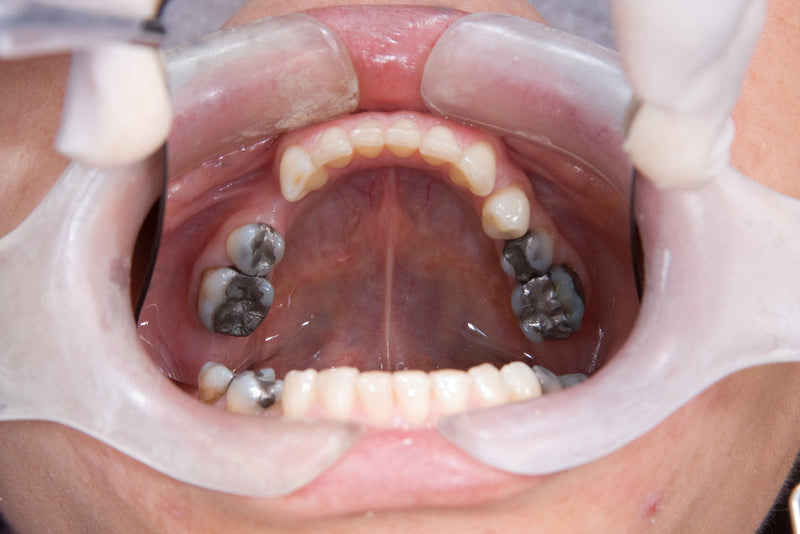

Today we're going to explore the world of cavities. Cavities, also known as dental caries, are areas of tooth decay that create holes in the teeth. They're often the result...